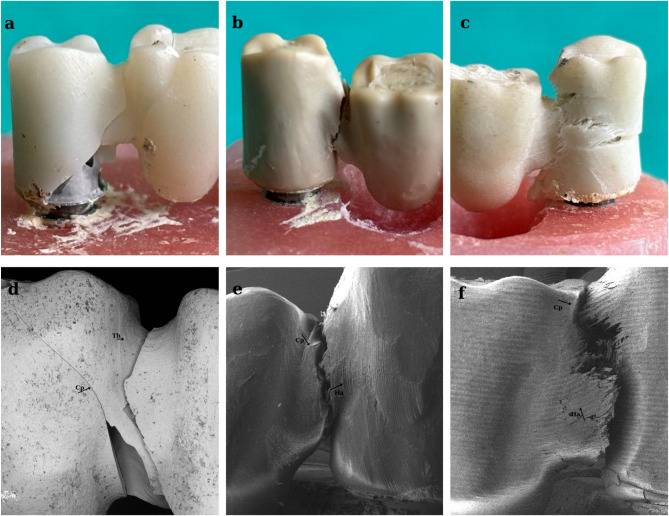

As can be seen in Fig. 3, the fracture line was clearly observed in the zirconia material (Fig. 3a), As the fragility of the material increased, so it tended to break in the weakest zone. In ductile materials such as PEEK and FRC, plateau area is formed before permanent deformations of the material occur under compressive stress. Plateau areas are the second stage and vary depending on the ductility of the material. Deformation hardening occurs in the third stage due to increased stress. This results in increased resistance of the prosthetic material known as the energy absorption limit (toughness) [19]. In GroupPEEK and GroupFRC, ruptures were seen after the occurrence of mass bending due to elastic deformation (Figs. 3b, c).

Fig. 3.

Images of the fractures in the different substructure materials

Fracture line of GroupZir(a), GroupPEEK(b), GroupFRC(c); SEM images of GroupZir(d), GroupPEEK(e), GroupFRC(f) FDP specimens after compression tests. Cp: crack propagation, Ha: hackles, Th: twist